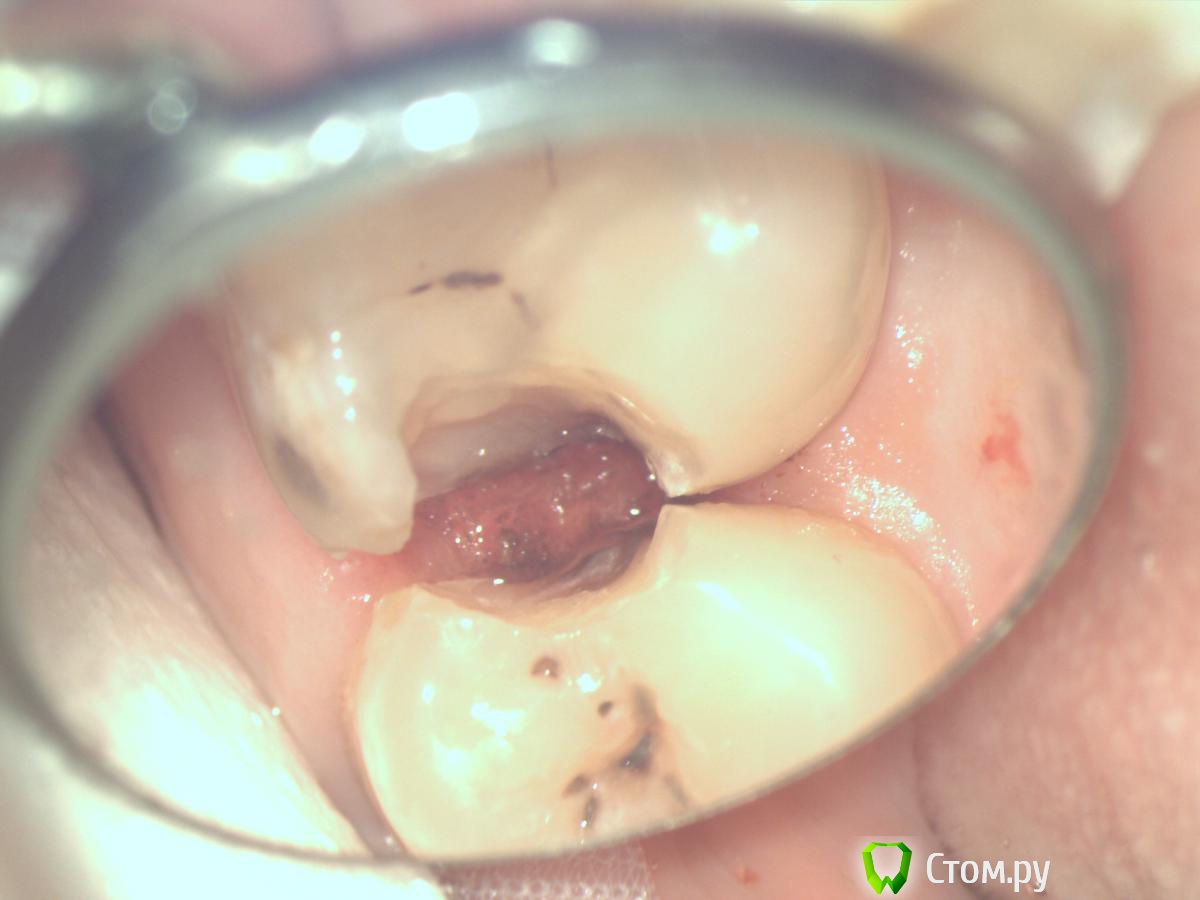

Dr.Sham Опубликовано 4 сентября, 2014 Поделиться Опубликовано 4 сентября, 2014 В клинику обратился пациент в возрасте чуть больше 30 лет. Сейчас проходит санацию перед ортодонтией.Мезиально/дистально на всех зубах в боковых отделах выявляются дефектные реставрации и под ними кариесы корней на 3-4 мм под десну. На "интактных зубах" такая же картина. Парадонтальных проблем вестибулярно, небно нет, борозда 1 мм, а мезиально-дистально такие карманы с кариесами корней.Предстоит лечение брекетами.Проблема №1 как реставрировать такие зубы сейчас?Проблема №2 что будет с ними после ортодонтии? Коффер так глубоко под десну не установить, матрицу не обжать, накладки...оттиск сниму, а, фиксируясь, не заизолировать поле, а потом не вычистить цемент. Ссылка на комментарий

Л Ю С Я Опубликовано 4 сентября, 2014 Поделиться Опубликовано 4 сентября, 2014 Фото после препа? Коффер сплит дамом, индивидуализировать матрицы. Я толкаю сначала фумку, затем клин, потом опять фумку подтыкиваю Ссылка на комментарий

Dr.Sham Опубликовано 24 сентября, 2014 Автор Поделиться Опубликовано 24 сентября, 2014 Ссылка на комментарий